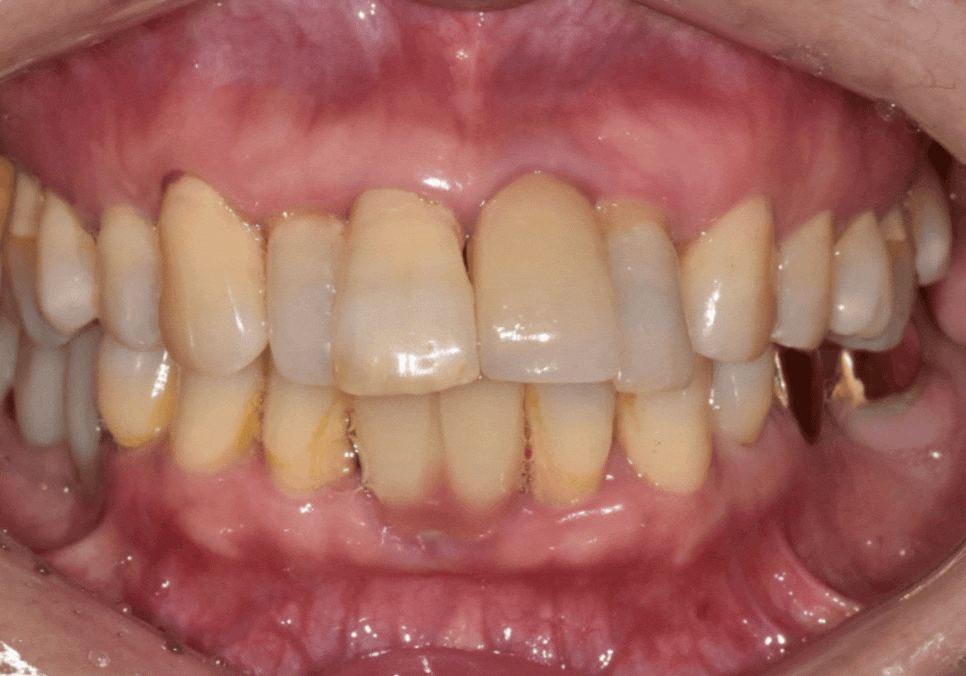

문제는 기존 임플란트 보철이

예전 치아 배열 기준으로

제작돼 있었다는 점이었는데요,

그 보철을 기준으로 새 보철을 맞추면

최종 결과가 다시

앞니가 튀어나와 보이는 형태로

갈 가능성이 있었습니다.

그래서 기존 임플란트는

고정체(뿌리)는 그대로 두고,

보철만 제거한 뒤,

앞니 라인을

덜 도드라져 보이도록

다시 설계했습니다.